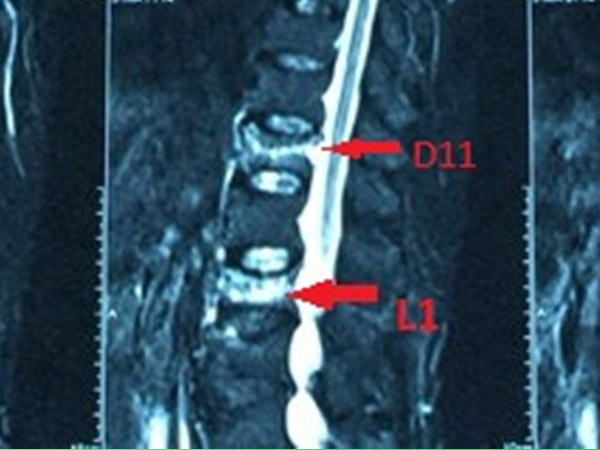

Tổng 75 đốt sống được bơm trong đó có 36 đốt ở cột sống ngực, 39 đốt ở cột sống thắt lưng. Đốt sống được bơm nhiều nhất là L4 với 12 bệnh nhân, tiếp theo là T12 với 11 bệnh nhân và T11 với 10 bệnh nhân. Ít nhất ở T7 với 1 bệnh nhân.

Tiêu chuẩn lựa chọn: bệnh nhân đau cột sống ngực – thắt lưng do xẹp đa tầng thân đốt sống loãng xương, không đáp ứng với điều trị nội khoa; đau cột sống ngực – thắt lưng và có hình ảnh phù nề tủy xương trên phim cộng hưởng từ (hình ảnh tăng tín hiệu trên thì T2 và STIR, giảm tín hiệu trên thì T1) kể cả không có giảm chiều cao thân đốt sống; không có dấu hiệu chèn ép thần kinh.